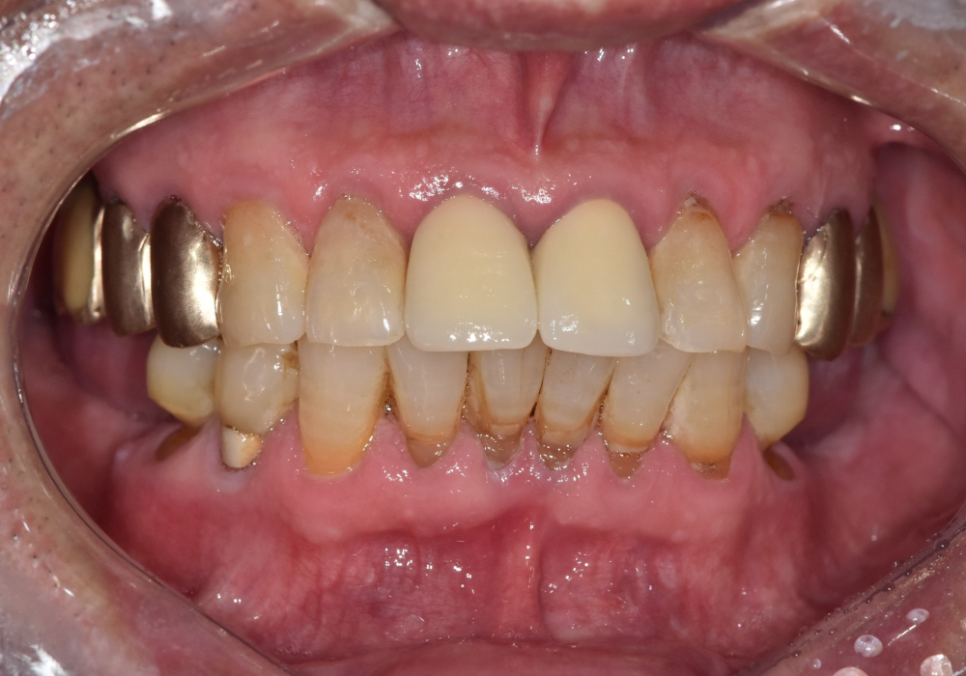

2개월 뒤 완성된 임플란트

2개 발치했는데, 1개만 심어도 된다구요? 강동구 임플란트 가격 줄이는 방법

약 2개월 뒤 보철이 완성됐고,

임플란트를 2개 심지 않더라도

아래 앞니 라인이

자연스럽게 정리되었습니다.

이번 케이스의 핵심은,

환자분의 비용 부담과

구조적, 기능적 안정성을 함께 고려해

무리 없는 설계로

과잉 수술을 줄였다는 점입니다.

241228

두 개를 발치했다고 해서

항상 임플란트도

두 개가 정답은 아닐 수 있습니다.